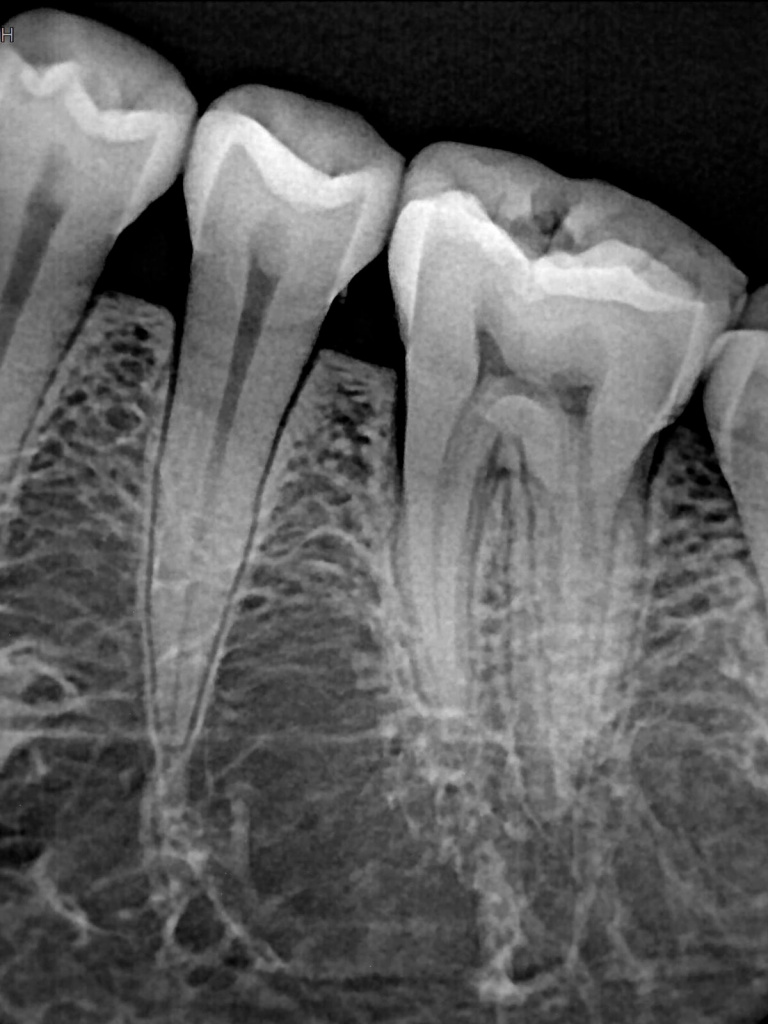

Снимки, сделанные с помощью нового визиографа Handy (см. рис. 3), говорят сами за себя. Рассмотрим слой за слоем, что скрывается под герметичным корпусом датчика и противоударным слоем, чтобы понять преимущества устройства.

Рис. 3. Снимки, сделанные с помощью визиографов HDR-500 и HDR-38